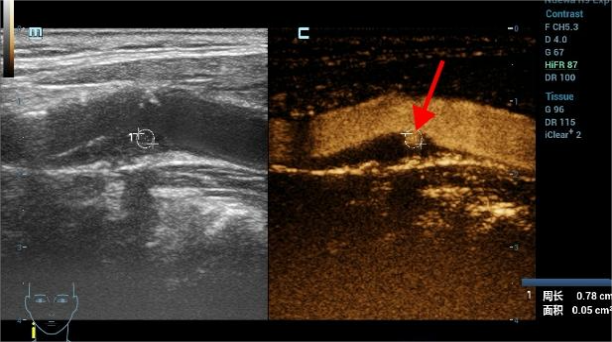

05颈动脉的超声造影报告怎么看?

我们把颈动脉斑块造影分做4级:I~IV级依此显示新生血管从无到有,逐步增多。其中I~II级为稳定斑块,II~IV级为易损斑块。我们可以借助超声造影清晰地显示斑块的表面溃疡,整体形态等结构; 还能清晰显示动脉管腔狭窄的位置以及是否合并闭塞,指导临床进一步干预及评估干预效果。